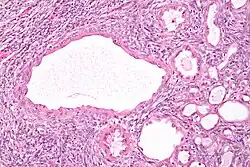

| Micrograph of a cystic nephroma (left of image). Normal kidney is seen on the right. H&E stain. | |

A cystic nephroma, also known as multilocular cystic nephroma, mixed epithelial stromal tumour (MEST) and renal epithelial stromal tumour (REST),[1] is a type of rare benign kidney tumour.

Cystic nephromas are diagnosed by biopsy or excision. It is important to correctly diagnose them as, radiologically, they may mimic the appearance of a renal cell carcinoma that is cystic.[2]

The characteristics of cystic nephromas are:

- Cysts lined by a simple epithelium with a hobnail morphology, i.e. the nuclei of the cyst lining epithelium bulges into the lumen of the cysts,

- Ovarian-like stroma that has a:

- Spindle cell morphology, and has a

- Basophilic cytoplasm.